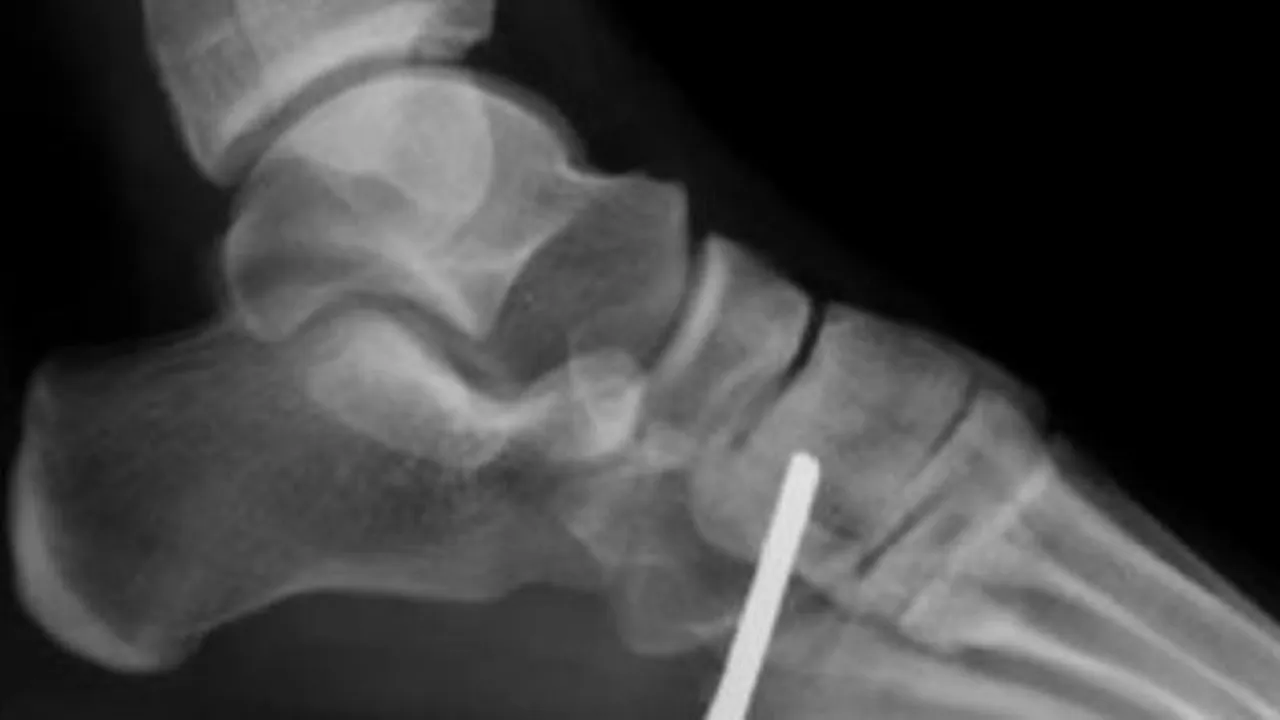

Cheia de la mașină, pe care tânărul o ținea în buzunar, i s-a înfipt în picior, în momentul în care a căzut pe spate, în timpul unui exercițiu.

Băiatul din statul Illinois a fost dus de urgență la spital. Medicii au avut nevoie de șapte ore pentru a îndepărta cheia.

În urma unor radiografii, specialiștii au constatat că obiectul nu a cauzat nicio ruptură a oaselor. De asemenea, nici sistemul nervos nu a fost afectat.